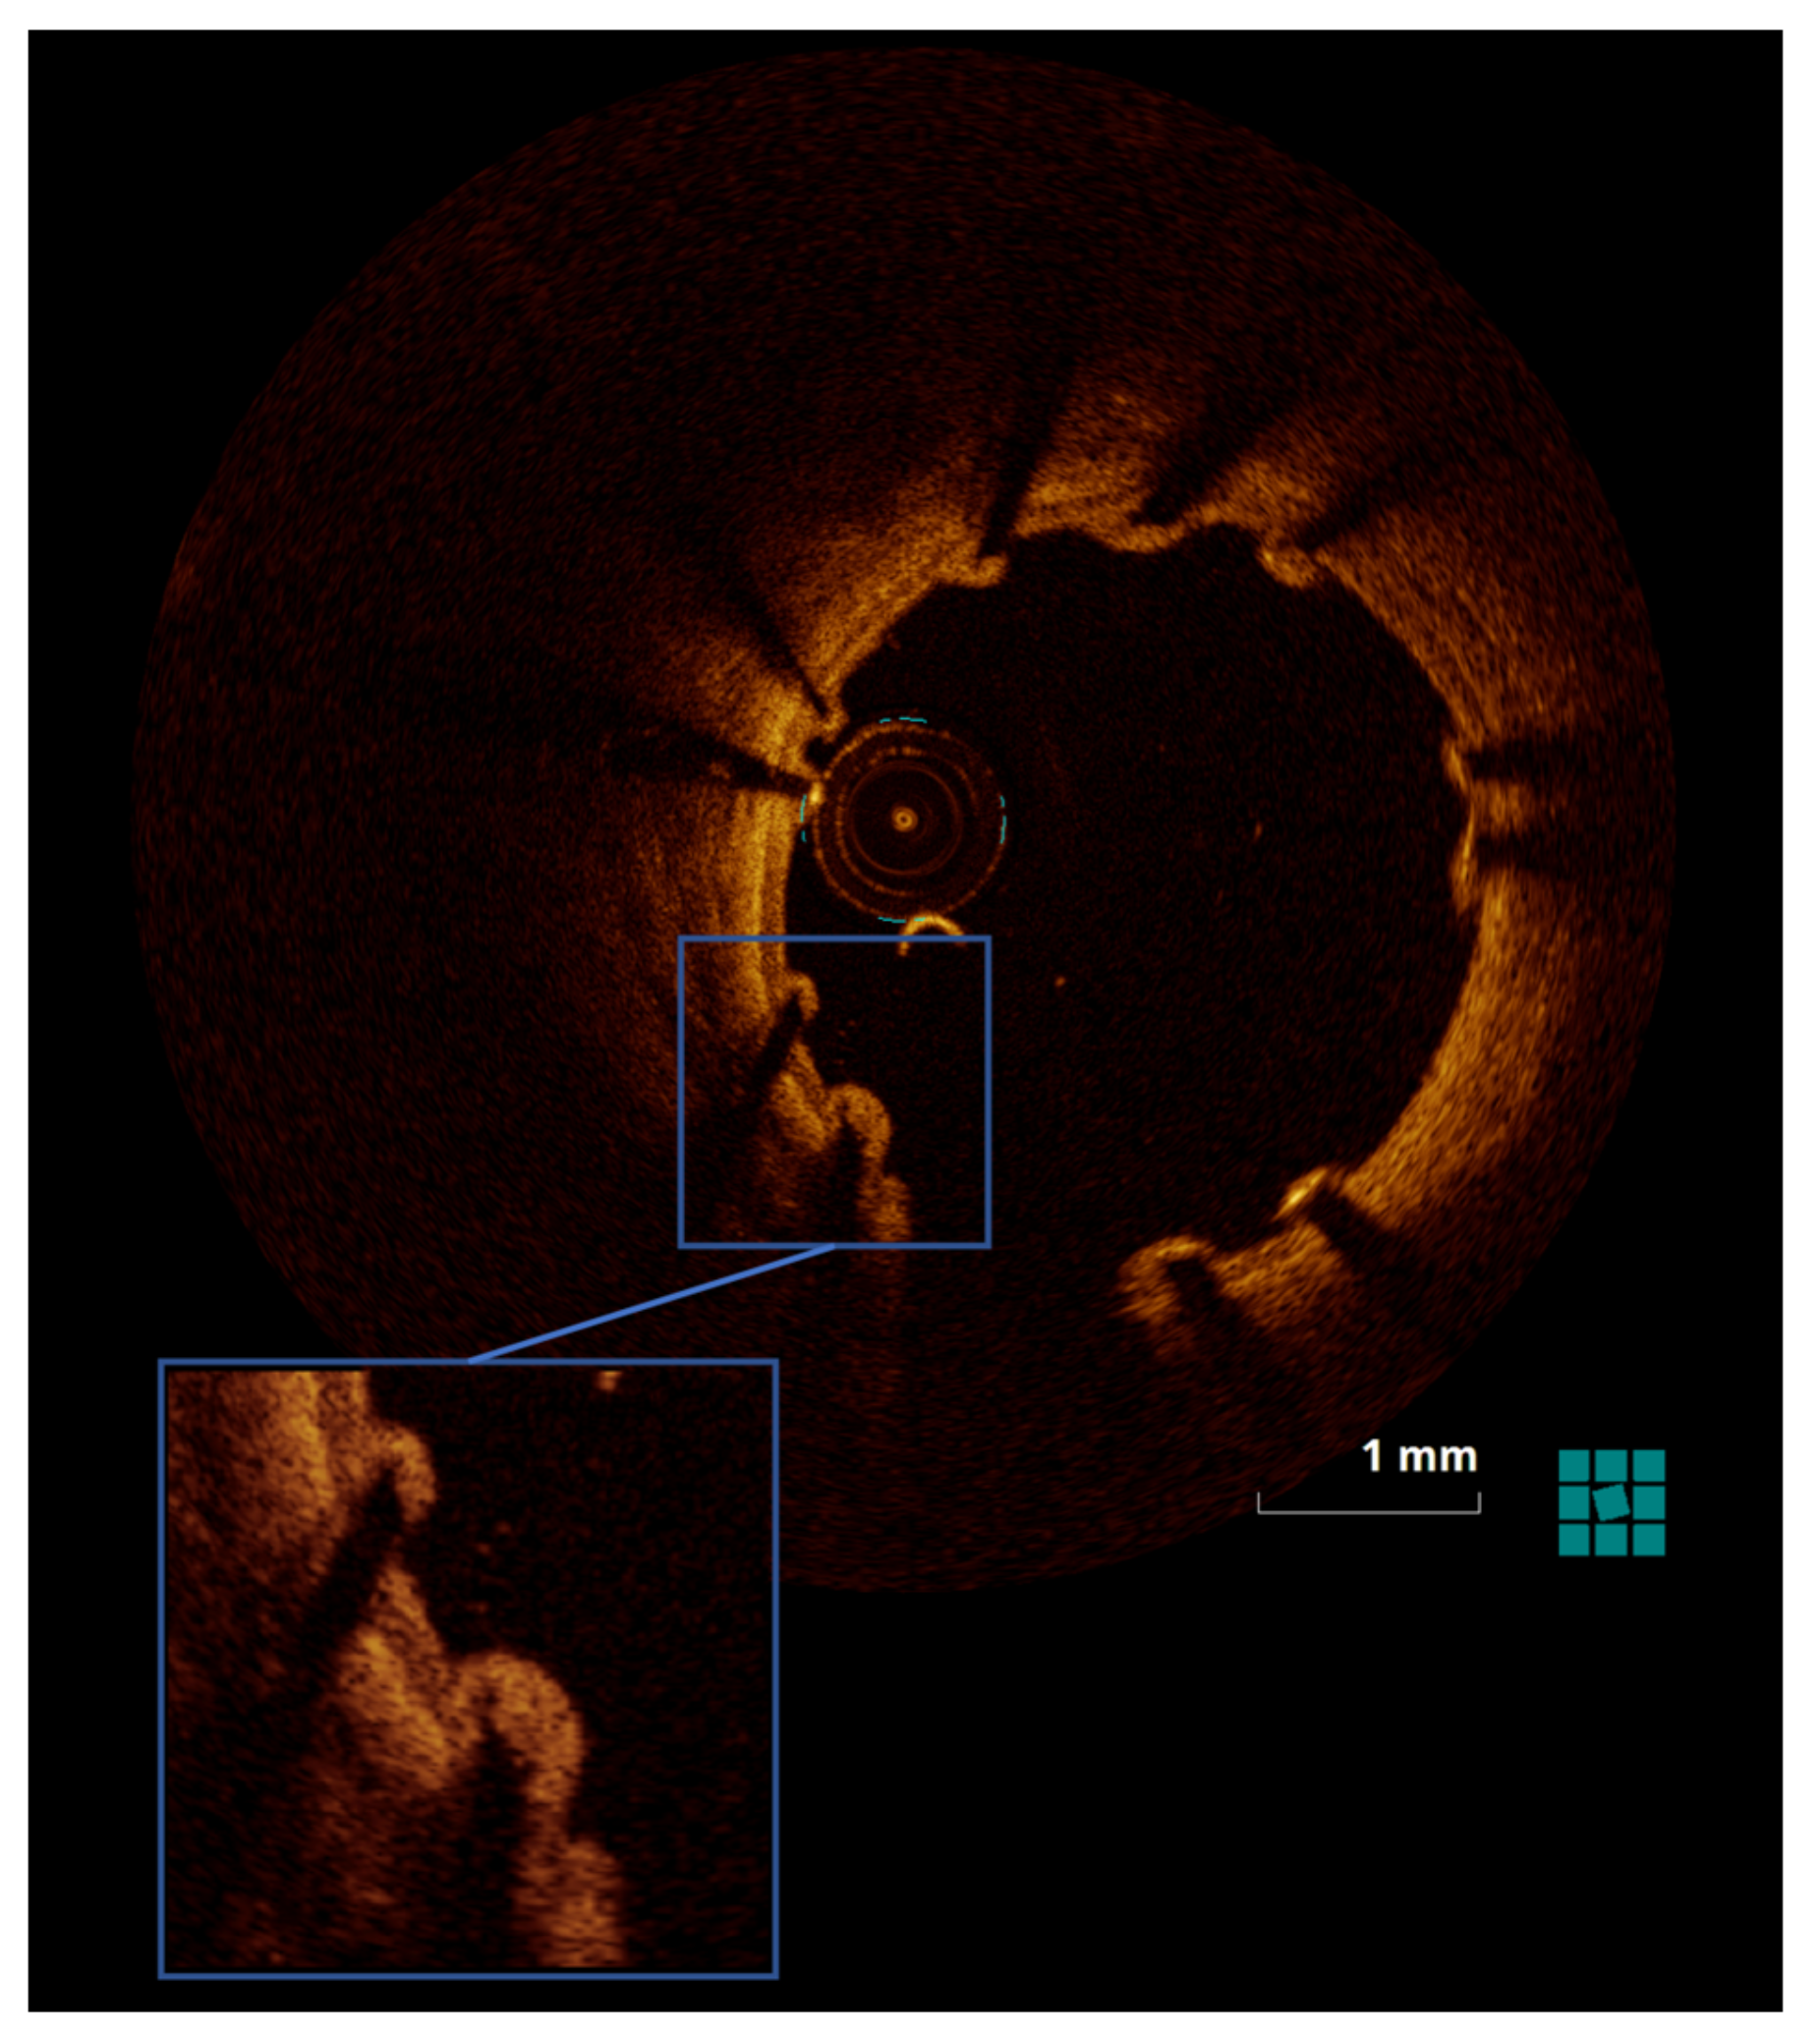

2.4.2. OCT

3.1.2. OCT